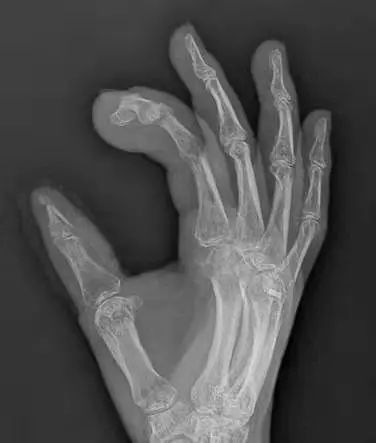

(术后三个月)

术后,经手足显微手外科医护人员的精心治疗和护理,辅以针对性的康复训练,罗先生受伤严重的左手正逐渐恢复,原本一直不安的心终于放下了,对给予左手重生的医护人员充满感激之情。